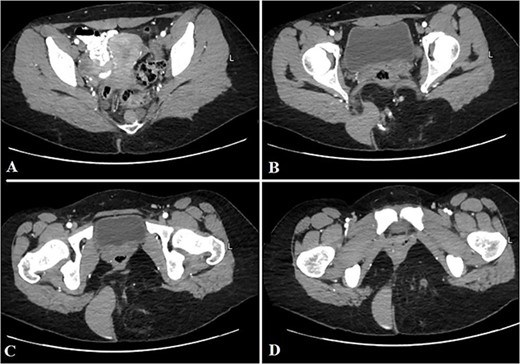

Contrast-enhanced computed tomography (CT) showed an ill-defined mass-like lesion in the gluteal region. The lesion consists of mixed tissue (fat predominantly, fluid and calcifications) and is seen exerting mass effect on the adjacent muscles and extending into the ischioanal, ischiorectal fossa and pre-coccygeal region (Figs 1 and 2).

Selected axial CT cuts of the pelvis with oral and IV contrast (Arterial phase) from above downward (A–D), showing the mentioned gluteal mass measuring about 9 × 15 × 0.5 cm3. The boundaries of the lesion were not clearly defined and the dimensions were assumed based on its mass effect on the adjacent structures. The lesion consisted of mixed tissues (fat predominantly, fluid and calcifications). The fluid portion appeared on the right aspect of the gluteal region with high density, indicating mucinous/proteinaceous content. Extensions into the ischio-rectal fossa are noted with minimal pre-coccygeal components seen as well.